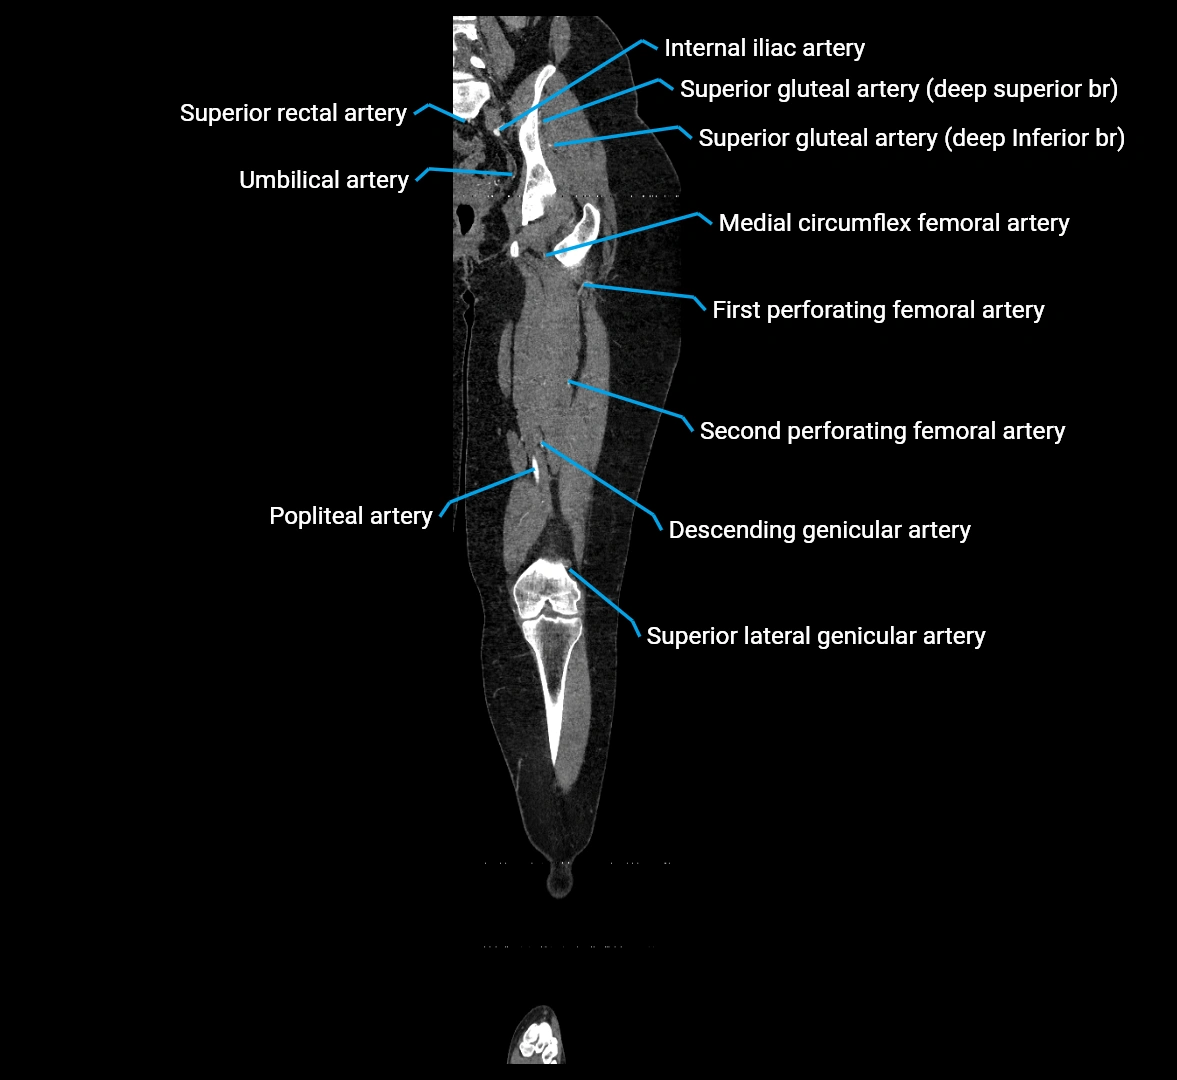

CT images

image

Contrast-enhanced CT (CTA):

• Gold standard for abdominal aortic imaging

• Provides excellent detail of lumen, wall, aneurysm, thrombus, and branch vessels

• Multiplanar and 3D reconstructions help in aneurysm measurement, stent graft planning, and dissection evaluation

• Unpaired visceral branches: celiac trunk, superior mesenteric artery (SMA), inferior mesenteric artery (IMA)

• Paired visceral branches: middle suprarenal arteries, renal arteries, gonadal arteries (testicular or ovarian)

• Parietal branches: inferior phrenic arteries, lumbar arteries, median sacral artery

• Terminal branches: right and left common iliac arteries